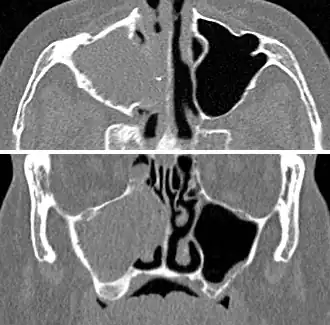

For cases of maxillary sinusitis, limited field CBCT imaging, as compared to periapical radiographs, improves the ability to detect the teeth as the sources for sinusitis. A coronal CT picture may also be useful.[60]

-

CT of chronic sinusitis -

CT scan of chronic sinusitis, showing a filled right maxillary sinus with sclerotic thickened bone -

Maxillary sinusitis caused by a dental infection associated with periorbital cellulitis -

Frontal sinusitis -

X-ray of left-sided maxillary sinusitis marked by an arrow. There is a lack of air transparency, indicating fluid in contrast to the other side.